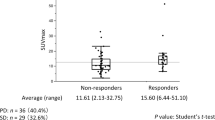

The median SUVmax was 5.9 for all subjects, 4.5 for stage IA, 8.4 for stage IB, and 10.9 for stage IIB (Fig. 1). The optimal cutoff value of SUVmax was 8.2 for all subjects. No optimal cutoff value of SUVmax could be established for specific stages with acceptable sensitivity and specificity for predicting the overall survival. No stage-specific analysis was performed for stage IIA due to the small number of subjects.

In univariate proportional hazards (Cox) regression analysis, each doubling of SUVmax [i.e., each log (base 2) unit increase in SUVmax] was associated with a 1.28-fold [95% confidence interval (CI): 1.0–1.6, p = 0.029] increase in hazard of death (Table 2). Kaplan-Meier survival analyses showed significant difference in overall survival when stratified by median SUVmax (Fig. 2) and optimal cutoff SUVmax (Fig. 3) in the whole group of cases (log-rank test, p = 0.018 and p = 0.004, respectively). The mean survival times of patients with SUVmax of primary tumor equal to or more than median value 5.9 and optimal cutoff value of 8.2 were 66.6 months and 58.9 months, respectively, compared with overall mean survival time of 73.5 months.

Univariate proportional hazards (Cox) regression analyses did not show any significant difference in survival by SUVmax when data were stratified according to the pathological stage (p = 0.119, p = 0.818, and p = 0.882 for pTNM stages IA, IB, and IIB, respectively, Table 2).

Kaplan-Meier survival analyses also did not detect any significant survival differences in any of the pathological stage subgroups considered when patients were stratified according to the stage-specific median SUVmax (log-rank test, p = 0.071, p = 0.682, and p = 0.928 for pTNM stages IA, IB, and IIB, respectively, Figs. 5, 6, and 7).